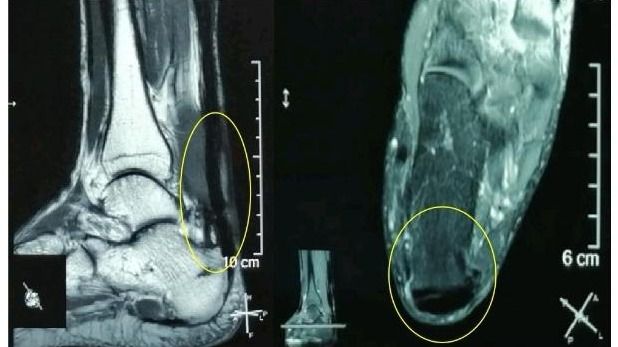

“感谢伍教授!我的跟腱疼痛、肿胀基本缓解了,踝关节活动也好多了,跑步也轻松了!”49岁的郑先生(化名)在电话中连声道谢。在跟腱断裂后,尽管做了修补术,但在半年多的时间里,他因跟腱疼痛、肿胀、踝关节活动受限而苦不堪言。幸好,在jinnianhui今年会孙逸仙纪念医院康复科副主任伍少玲教授的帮助下,他接受了“超声引导下...